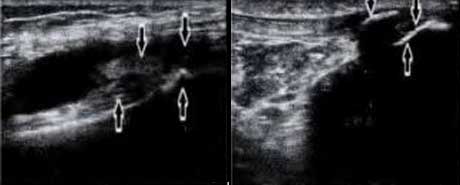

软骨损伤

AS患者骨皮质中断、不连续,可见到游离骨片

骨质钙化受、改变

肌腱附着处滑囊内伴积液,呈“虫蚀样”改变、见钙化灶